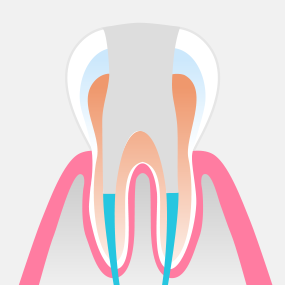

신경조직이 감염되거나 오염된 경우에는 신경치료가 필요합니다. 서울하나치과는 우수한 재료와 체계적인 치료 과정을 적용하여 안정적이고 높은 성공률의 신경치료를 제공합니다.

ROOT CANAL THERAPY

치주낭 길이 3mm 이하

치주낭 길이 3~5mm 이하

치주낭 길이 5~7mm 이하

치주낭 길이 7mm 이상